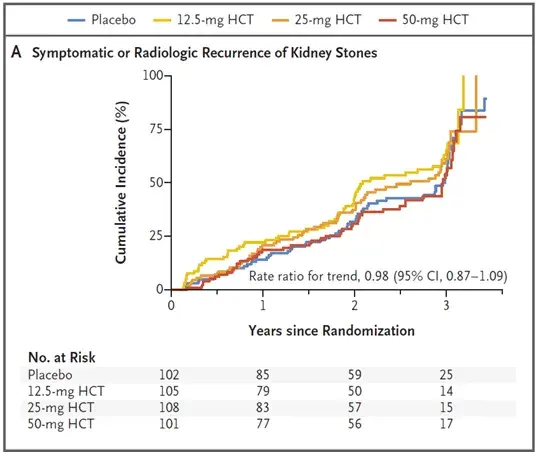

Highlights ASN 2025: Novas Fronteiras em IgA, descontinuação de Hemodiálise e o uso do Ômega-3 nos dialíticos

Highlights ASN 2025: Novas Fronteiras em IgA, descontinuação de Hemodiálise e o uso do Ômega-3 nos dialíticos